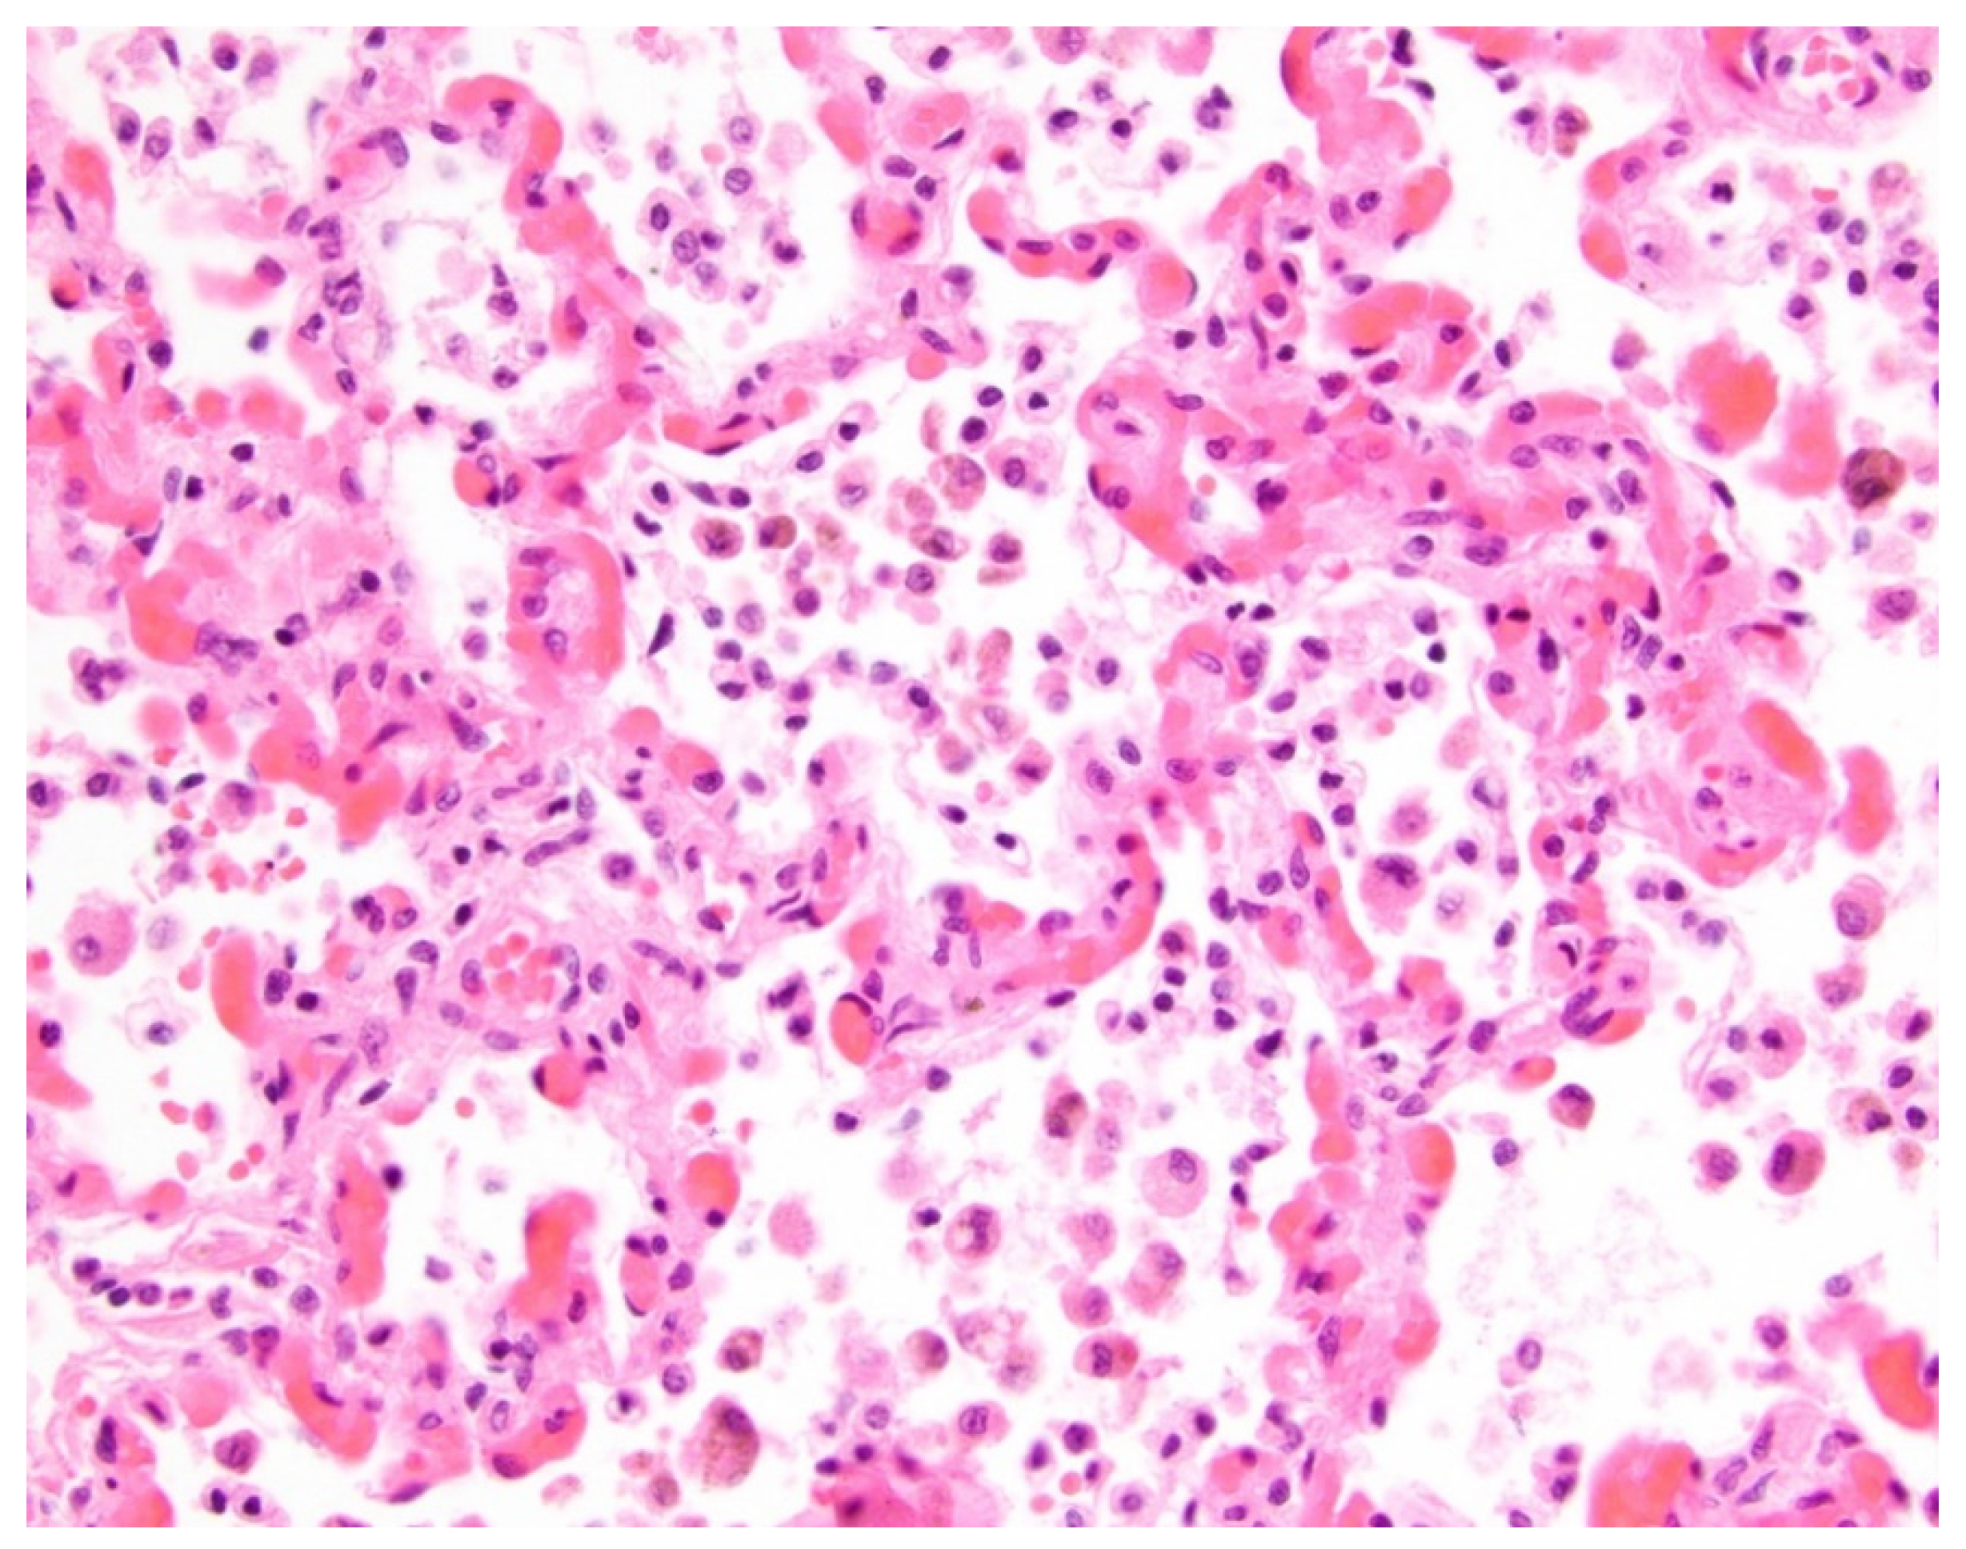

- Pogoriler, J.E.; Kulik, T.J.; Casey, A.M.; Baird, C.W.; Mullen, M.P.; Jenkins, K.J.; Vargas, S.O. Lung pathology in pediatric pulmonary vein stenosis. Pediatr. Dev. Pathol. 2016, 30, 219–229. [Google Scholar] [CrossRef]

- Callahan, R.; Gauthier, Z.; Toba, S.; Sanders, S.P.; Porras, D.; Vargas, S.O. Correlation of intravascular ultrasound with histology in pediatric pulmonary vein stenosis. Children 2021, 8, 193. [Google Scholar] [CrossRef] [PubMed]